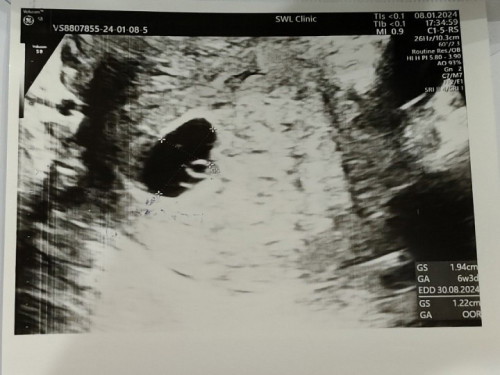

ท้องที่สองค่ะเพิ่งไปฝากครรภ์วันนี้ อายุครรภ์9w6d(นับจากประจำเดือนครั้งสุดท้าย) แต่พอซาวด์กลับเจอแต่ถุงไข่แดง ซึ่งตอนท้องแรกอายุครรภ์ประมาณนี้ คือน้องเริ่มเป็นเหมือนทารกแล้วนะคะ มีแม่ๆท่านไหนเป็นแบบนี้บ้างคะ? ขอบคุณทุกความคิดเห็นเลยนะคะ หมอนัดอีก2อาทิตย์ค่ะ ระหว่างนี้หมอบอกว่าถ้ามีเลือดออกก็ให้รีบไปหาหมอเลย เพราะก่อนมีคนแรก เราเคยแท้งมาก่อน2ครั้งค่ะ ก่อนหน้านี้กับตอนนี้ก็มีอาการปวดตรงท้องน้อยด้วยนิดหน่อย แต่ก็พยายามคิดว่าอาจเป็นการขยายตัวของมดลูกก็ได้🙂